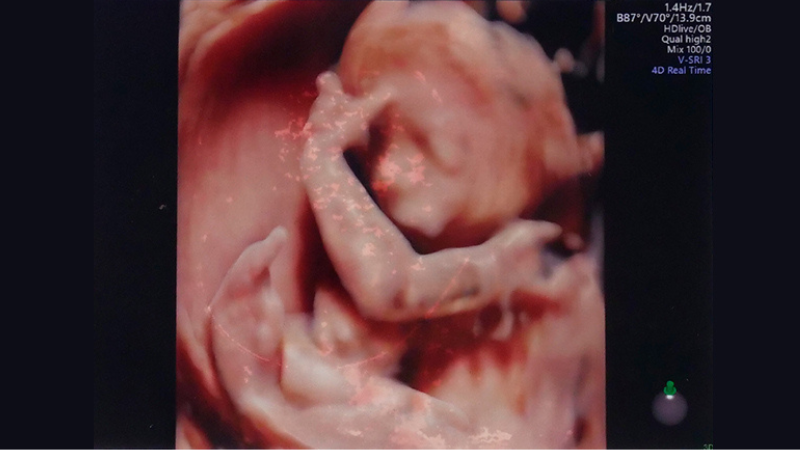

ダウン症児のエコー 誕生 告知 絶望 生まれた時の心境Down and UP。

妊娠中のエコー写真21枚で指摘できる、ダウン症の予兆東京・ミネルバクリニック。

医師監修 エコーでダウン症かわかるって本当?見え方や可能性があるときの対応を解説トモニテ。

エコー写真わかる?ダウン症の特徴 むくみ等 出生前診断のこころえ。

産婦人科医監修 4Dエコーでダウン症はわかる?鼻が低いと可能性あり?ダウン症の特徴が出る時期はいつ?ままのて。